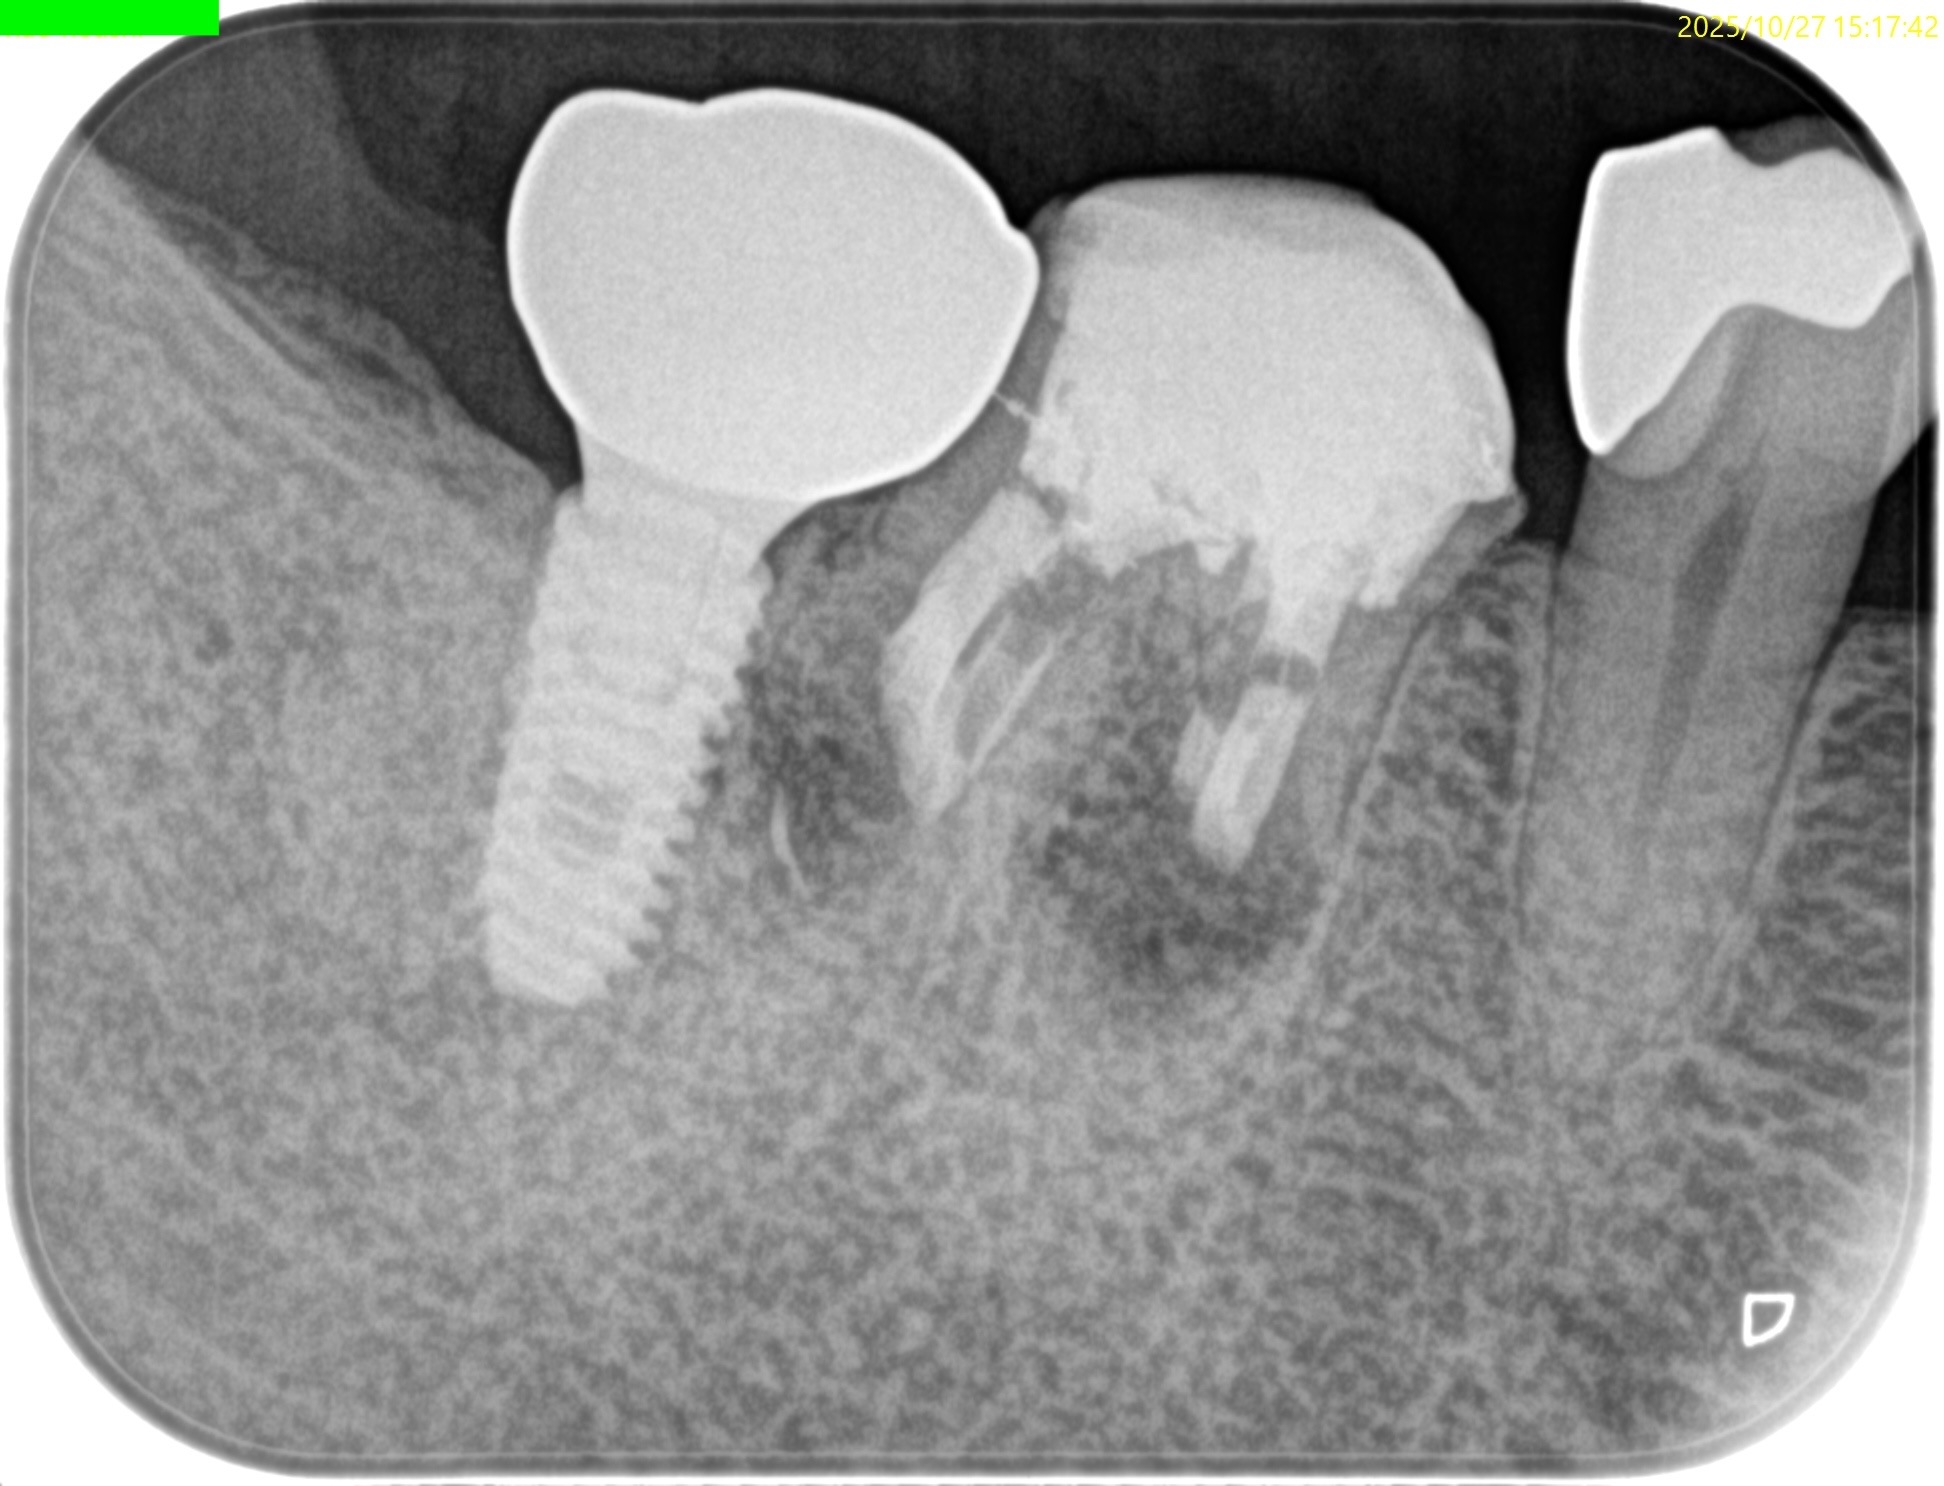

PA(2025.10.27)

近心はテーパー型、

遠心はパラレルで外れにくい感じのメタルポストコアだ。

MのApexに到達するにはCEJよりも12.5mm下方の歯槽骨を2mm削合(Osteotomy)しなければならない。

Apexを見つけたら3mm切断するがこの時の頬舌的な幅径が6.3mmだ。

リンデマンバーの半分よりも長い。

またDはApexに到達するには、CEJよりも13mm下方の歯槽骨を3mm削合する必要がある。

術後にPA, CBCTを撮影した。

気泡はあるが問題はないとして縫合した。